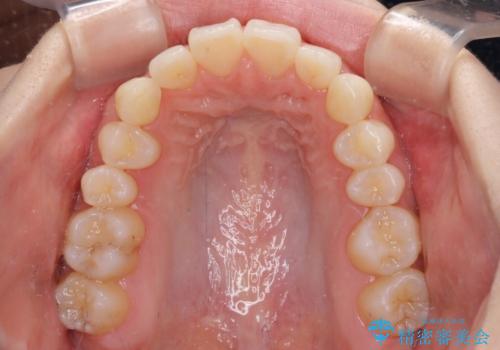

狭い上顎骨を拡大 急速拡大装置を併用したインビザライン矯正

- 前歯のクロスバイトや残存している乳歯を気にして来院された患者様です。

上顎骨の幅が下顎骨よりも小さいので、拡大装置により骨幅を広げて上下関係を改善し、その後インビザラインにて歯並びを整えることとしました。

上下の骨幅を改善したことで、スムーズに歯列矯正を行うことができました。

通院ペースが守れず治療期間が長くかかってしまいました。